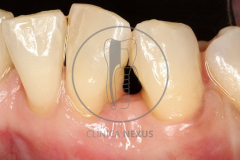

Tratamiento de defectos periodontales infraóseos en sector antero-inferior empleando gel de amelogeninas (Emdogain®) en combinación con un aloinjerto óseo (Biobank®). Paciente de 64 años, sin problemas médicos de relevancia, que presenta una periodontitis leve generalizada, pero asociada a presencia de defectos óseos verticales profundos a nivel de los espacios interdentales entre los caninos y los incisivos laterales inferiores. Tras la pertinente fase higiénica, se llevó a cabo una cirugía periodontal regenerativa, en la que, tras eliminar el cálculo subgingival (factor causal), se empleó una combinación de amelogeninas con un aloinjerto, para promover la regeneración tisular del periodonto perdido. Las imágenes clínicas y radiológicas, al año de seguimiento, reflejan un resultado terapéutico óptimo, con regeneración completa del tejido periodontal y mejora del pronóstico de los dientes involucrados.